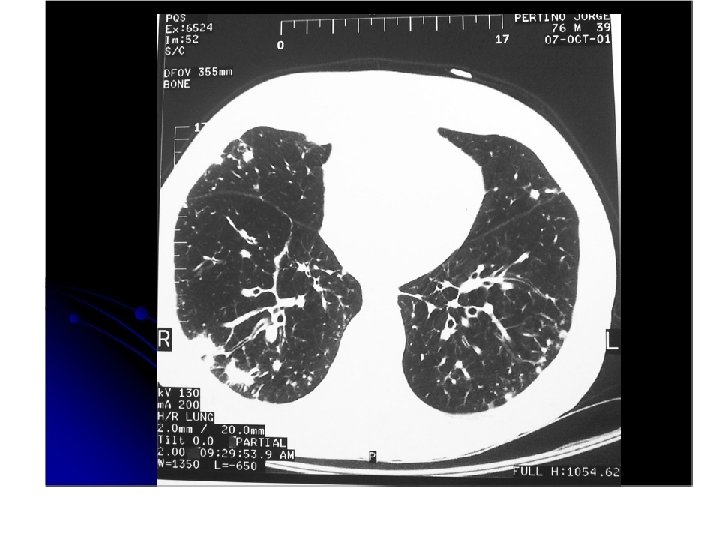

Aden ocarcinoma. • • • se puede presentar como un nódulo una zona de consolidación varios nódulos producen mucha secresión Sospechar en caso de neumonías que no se resuelven.

adenocarcinoma